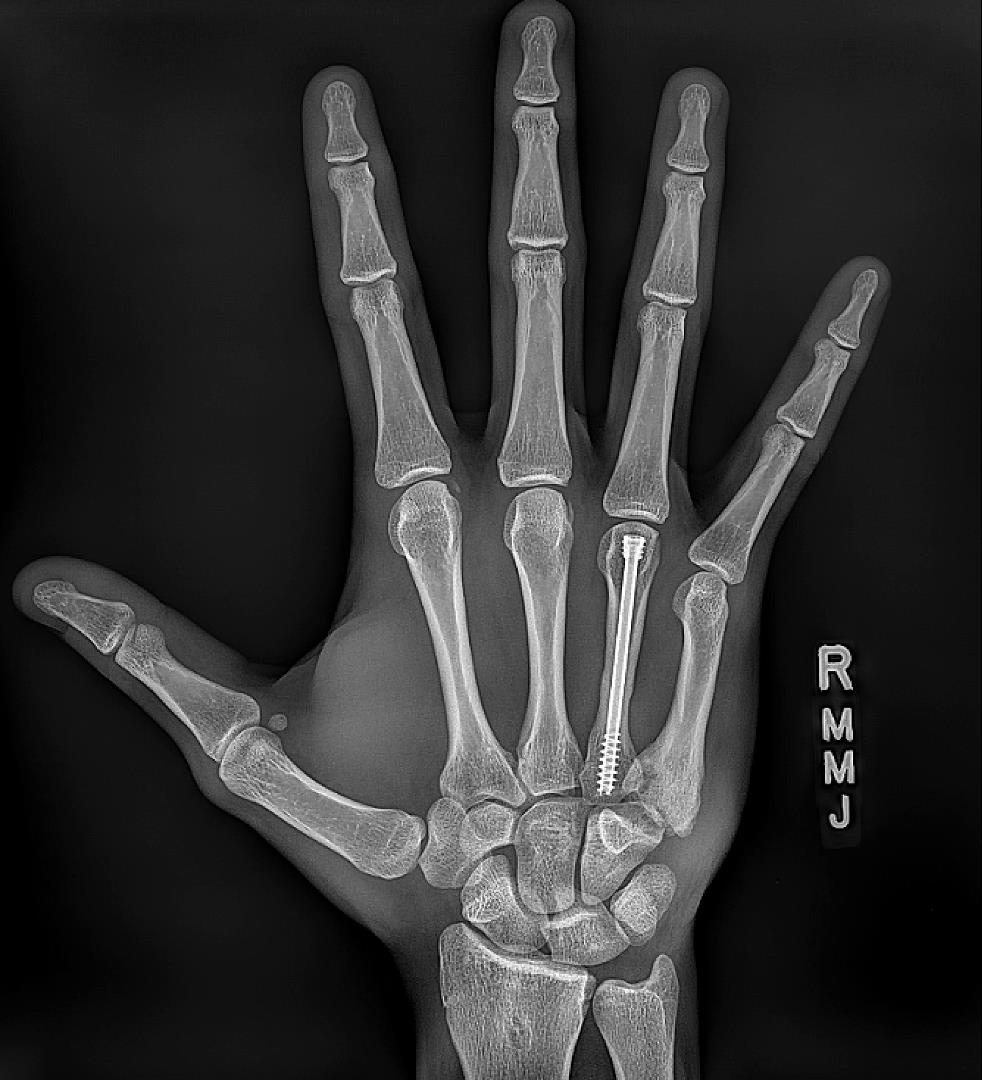

An 18-year-old male presents to your clinic with two weeks of right-hand pain. He reports punching the wall in the locker room after losing in the state championship. Radiographs from today’s visit are shown in Figures A-C. What is the most appropriate treatment at this time?

The radiographs show a displaced, angulated ring finger fracture with a comminuted, intraarticular fracture of the fifth metacarpal base. Given these fracture patterns and the time from injury, operative fixation of both injuries is the most appropriate treatment (Answer 1).

Figures A-C demonstrate a fourth metacarpal shaft fracture with angulation > 30 degrees. The fifth metacarpal base fracture is comminuted and intraarticular with carpometacarpal joint subluxation. Illustration A shows post-operative images of percutaneous pinning of the fifth metacarpal base fracture and intramedullary headless compress screw fixation of the fourth metacarpal. Illustration B shows 12-week post-operative imaging demonstrating union of both fractures.